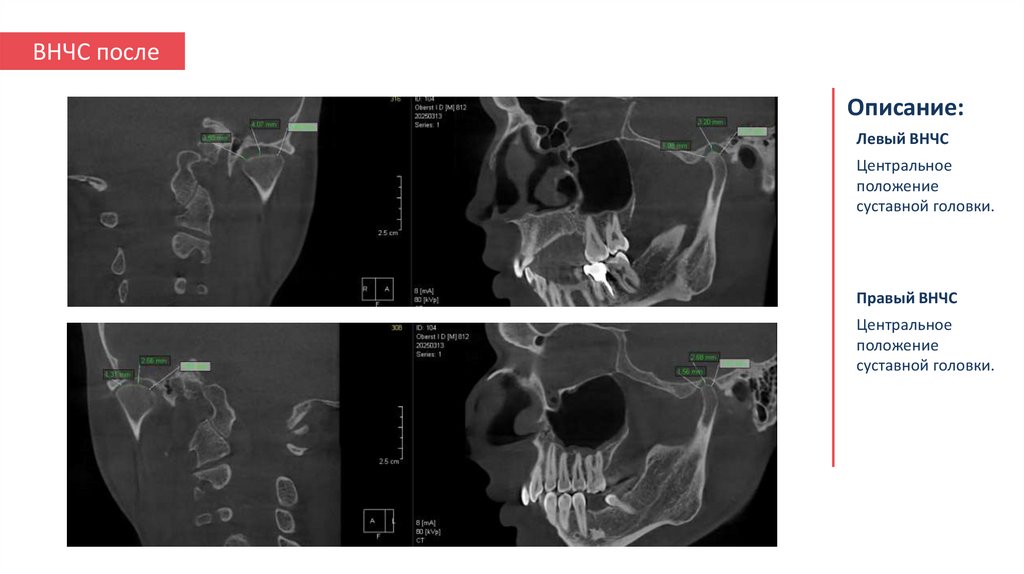

15. ВНЧС после

Описание:

Левый ВНЧС

Центральное

положение

суставной головки.

Правый ВНЧС